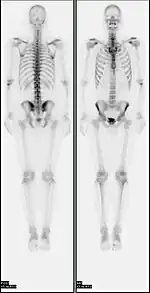

A nuclear medicine whole body bone scan. The nuclear medicine whole body bone scan is generally used in evaluations of various bone-related pathology, such as for bone pain, stress fracture, nonmalignant bone lesions, bone infections, or the spread of cancer to the bone.

Normal whole body PET/CT scan with FDG-18. The whole body PET/CT scan is commonly used in the detection, staging and follow-up of various cancers.

Abnormal whole body PET/CT scan with multiple metastases from a cancer. The whole body PET/CT scan has become an important tool in the evaluation of cancer.